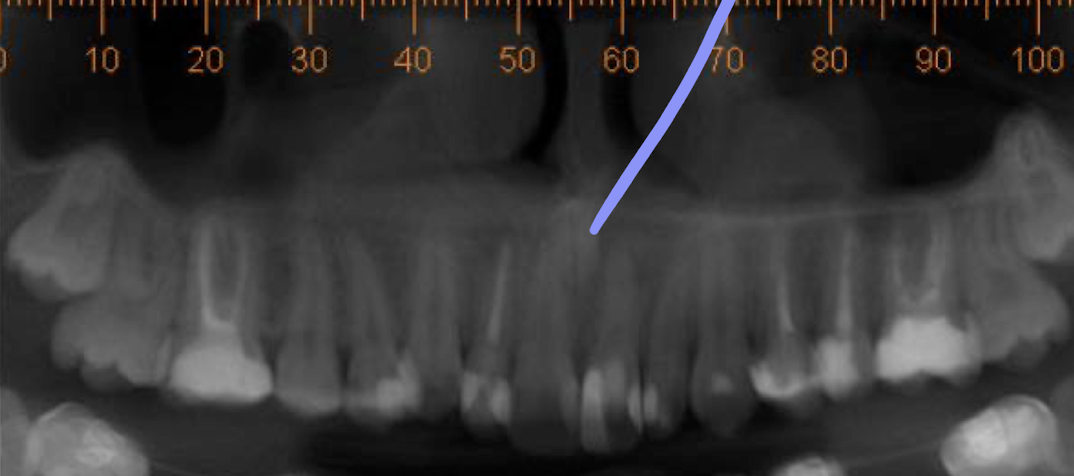

Is this x-ray, what teeth are missing?

Maxillary lateral incisors

What condition does this patient have that results in missing teeth?

Ectodermal dysplasia